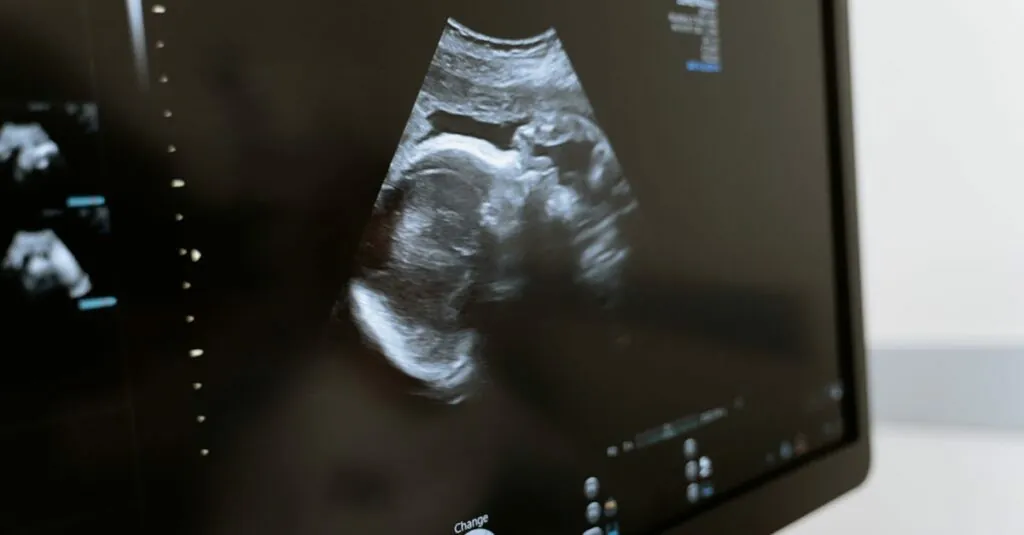

Ultrasound tech uses high-frequency sound waves to create images of organs and structures inside the body. Medical professionals frequently employ it in various settings, including obstetrics, cardiology, and emergency care. This non-invasive imaging method provides valuable information without exposing patients to harmful radiation. Beyond pregnancy monitoring, ultrasound assists in diagnosing conditions like gallstones, tumors, and cardiac issues, emphasizing its versatility and importance in healthcare.

Sound waves travel through a transducer when conducting an ultrasound. The device sends and receives these waves, which bounce off internal structures to form images. The echoes produced convert into visual representations displayed on a monitor. Often, gel is used on the skin to enhance sound wave conduction, improving image quality. Medical professionals interpret these visual outputs to assess patient conditions, offering immediate insights that drive timely decisions.

Medical diagnostics relies heavily on ultrasound for its non-invasive imaging capabilities. This technology allows for real-time visualization of internal structures, facilitating early detection of conditions. Obstetricians frequently perform ultrasounds to monitor fetal development, while cardiologists utilize it to assess heart health. Additionally, ultrasound aids in identifying abnormalities in organs like the liver and kidneys. Clinicians value these insights as they provide crucial information without exposing patients to radiation.